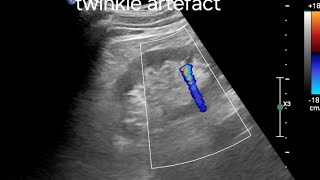

Twinkle Artifact on Color Doppler: Optimizing Detection of Renal Calculi

Ultrasound videos

Shared 1 year ago

0 views

[Ultrasound Case] Twinkling Artifact Revealing a Hidden Renal Stone

Awesome Ultrasound

Shared 7 months ago

637 views